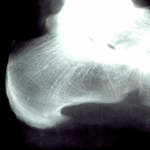

Může být vyvolána také vytvářením ostruhy. Jedná se o kostní trn, který vyrůstá z patní kosti. Vzniká jako kompenzační mechanizmus organizmu na přetížení, teda na přetížení úponů k patní kosti. Její přítomnost potvrzuje také rentgenový snímek. V případě ploché nohy úpony v chodidle vyvíjí tlak na patní kost, tudíž se vytvoří zánět okostice. Při obtížích trvalého charakteru se vytvoří kostní trn. Napínání úponů chodidla a jejich následovní zánětlivý proces nazýváme Plantaris fasciitis.